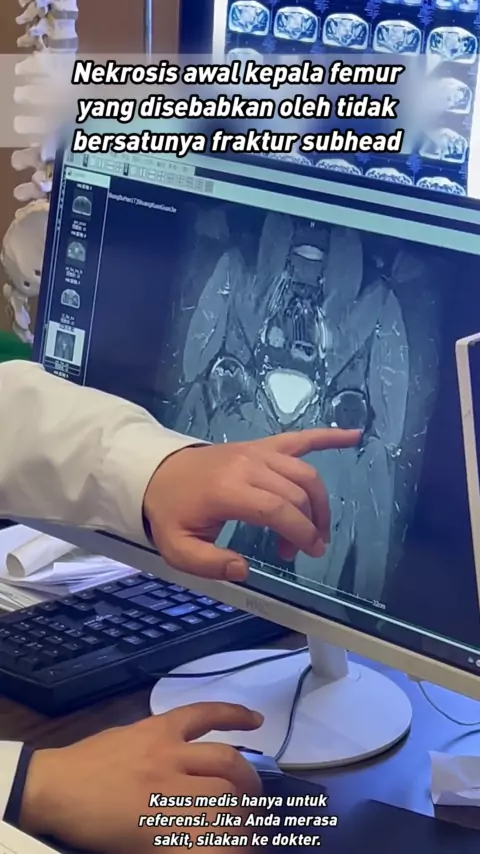

Osteonekrosis kepala femur dan transplantasi tulang drainase darah lebih cocok untuk pasien dengan kolaps yang kurang lengkap dari tahap kedua dan ketiga femur.

Nekrosis femoralis iskemik runtuh gambar rekonstruksi CT tiga dimensi Tahukah Anda seperti apa tulang femoralis Anda?